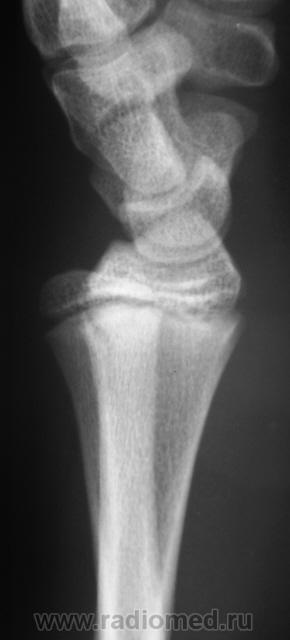

Пациент направлен врачом хирургом в рентгеновский кабинет для рентгенографии лучезапястного сустава. Произведено стандартное исследование. Ваше мнение уважаемые коллеги?

Продольный перелом лучевой кости.

Перелом - эпифезиолиз и продольная трещина в луче, смешение периферического фрагмента к тылу на приблизительно 20 градусов

Перелом луча без смещения. А вообще - головка локтевой кости смущает... или полупроекция?... Доснять бы в/3 предплечья - возможно повреждение Галеацци

В руководстве  Interpreting Trauma Radiographs Jonatan McConell et al. Blackwell Publishing 2005 p. 130 говорится о нормальном угле в боковой проекции в 10 -15 градусов. В представленном наблюдении угол составляет около 95-98 градусов (транспортира под рукой не оказалось), что говорит об угловом смещении периферического фрагмента к тылу на угол от  16 до 23 градусов.